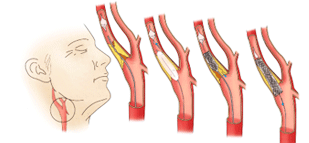

경동맥은 목의 좌우 양쪽에 있는 큰 혈관으로 심장에서 뇌로 피를 보내는 주된 혈관입니다. 뇌로 혈류를 공급하는 큰 혈관이기 때문에 이 혈관이 좁아지거나 막히게 되면 뇌졸중(중풍)의 위험도가 높아질 수 있습니다.

이 혈관을 초음파로 관찰하여 좁아진 정도! 협착의 정도를 평가하는 검사가 경동맥 초음파 검사이며 심혈관 질환 위험요인이 있는 분들이라면 정기적으로 받는 것이 좋습니다.

혈관의 벽 두께(IMT)를 측정: 혈관 벽이 두꺼워 졌는지를 확인하여 죽상동맥경화여부를 판단할 수 있습니다.

플라크의 여부: 지방 찌꺼기나 석회화 플라그가 있는지, 있다면 크기와 모양은 어떤지를 초음파로 체크할 수 있습니다.

혈류 속도와 방향: 혈류의 속도를 측정하고 장비에서 혈관에 컬러를 띄워 관찰하는데 협착의 유무나 얼마나 심한지를 평가 할 수 있습니다.